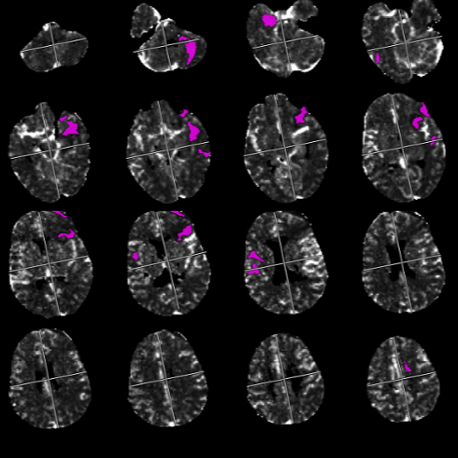

Patients' CT scans are uploaded, allowing our AI algorithm to generate a customized 3D model. This model is tailored specifically to meet the unique needs of each patient.

Our advanced AI technology analyses patients images and generates a customized 3D model of the implant, ensuring a perfect fit for the patient's skull.